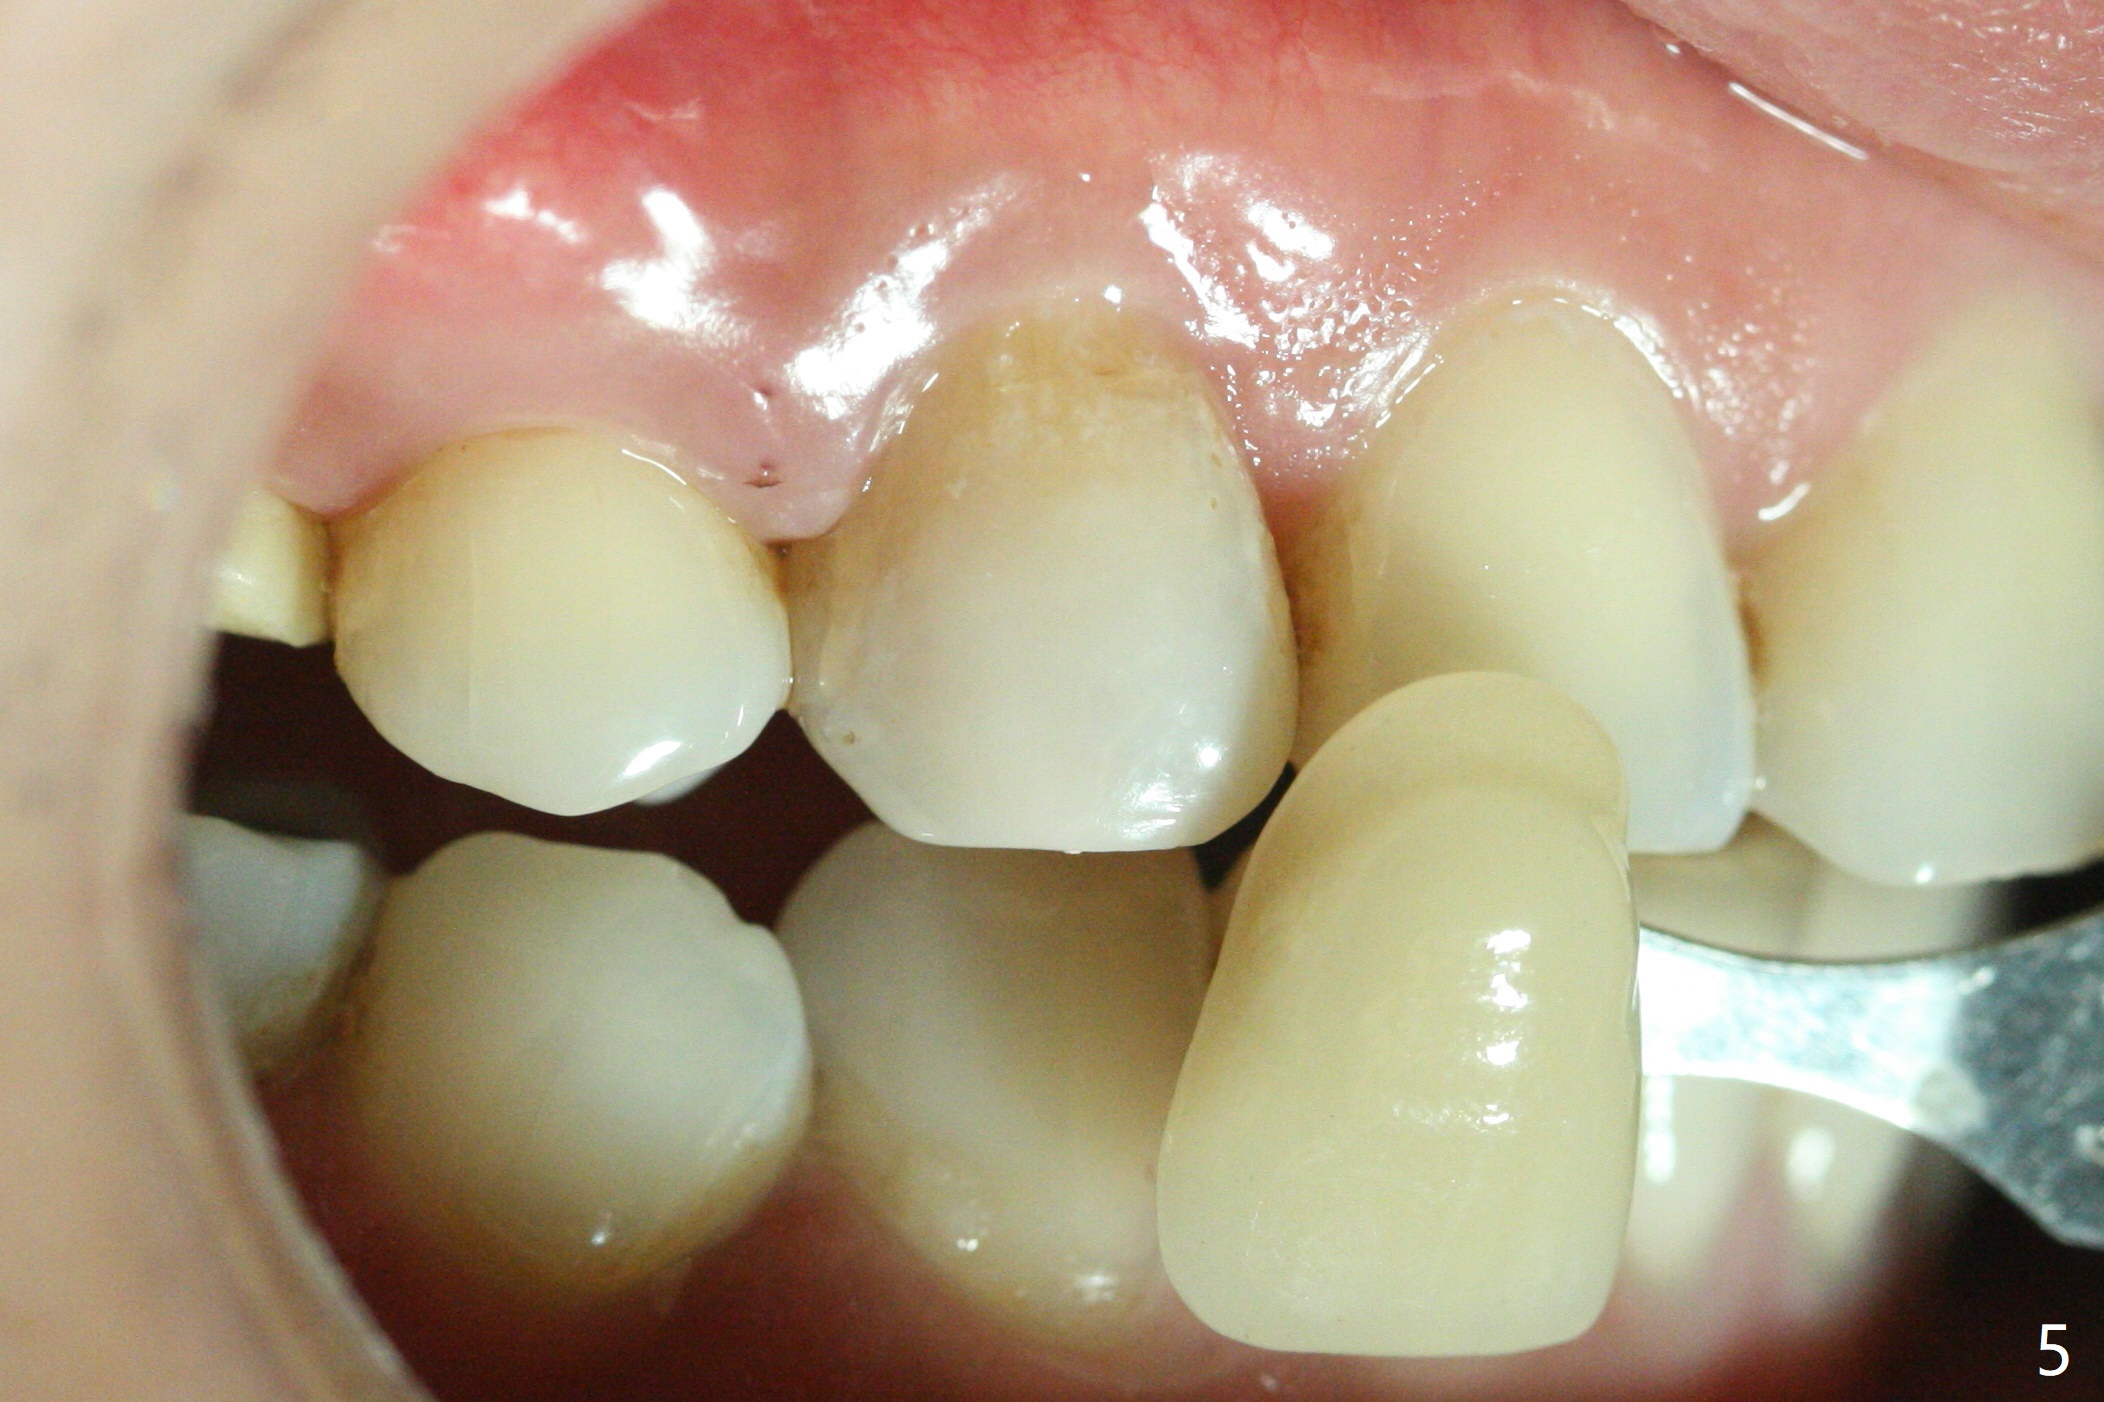

A 36-year-old woman (after #3 immediate implant and #31 socket preservation) wants to take care of the discolored canine 20 years post orthodontic treatment with extraction (Fig.1-3). RCT (Fig.4) appears to whiten the tooth (Fig.5 (A4)). The darkness appears to rebound 1 month post RCT, after removal of Gutta Percha for take home internal and external bleaching (Fig.6). The patient returns for composite after 3-week whitening (Fig.7,8). The shades of composite are bleach (flowable, C1) and B1 (packable, C2, Fig.9). The shade of the RCT tooth is compatible with that of the neighboring teeth 4 months post composite (Fig.10) when the implant at #3 has a new abutment.